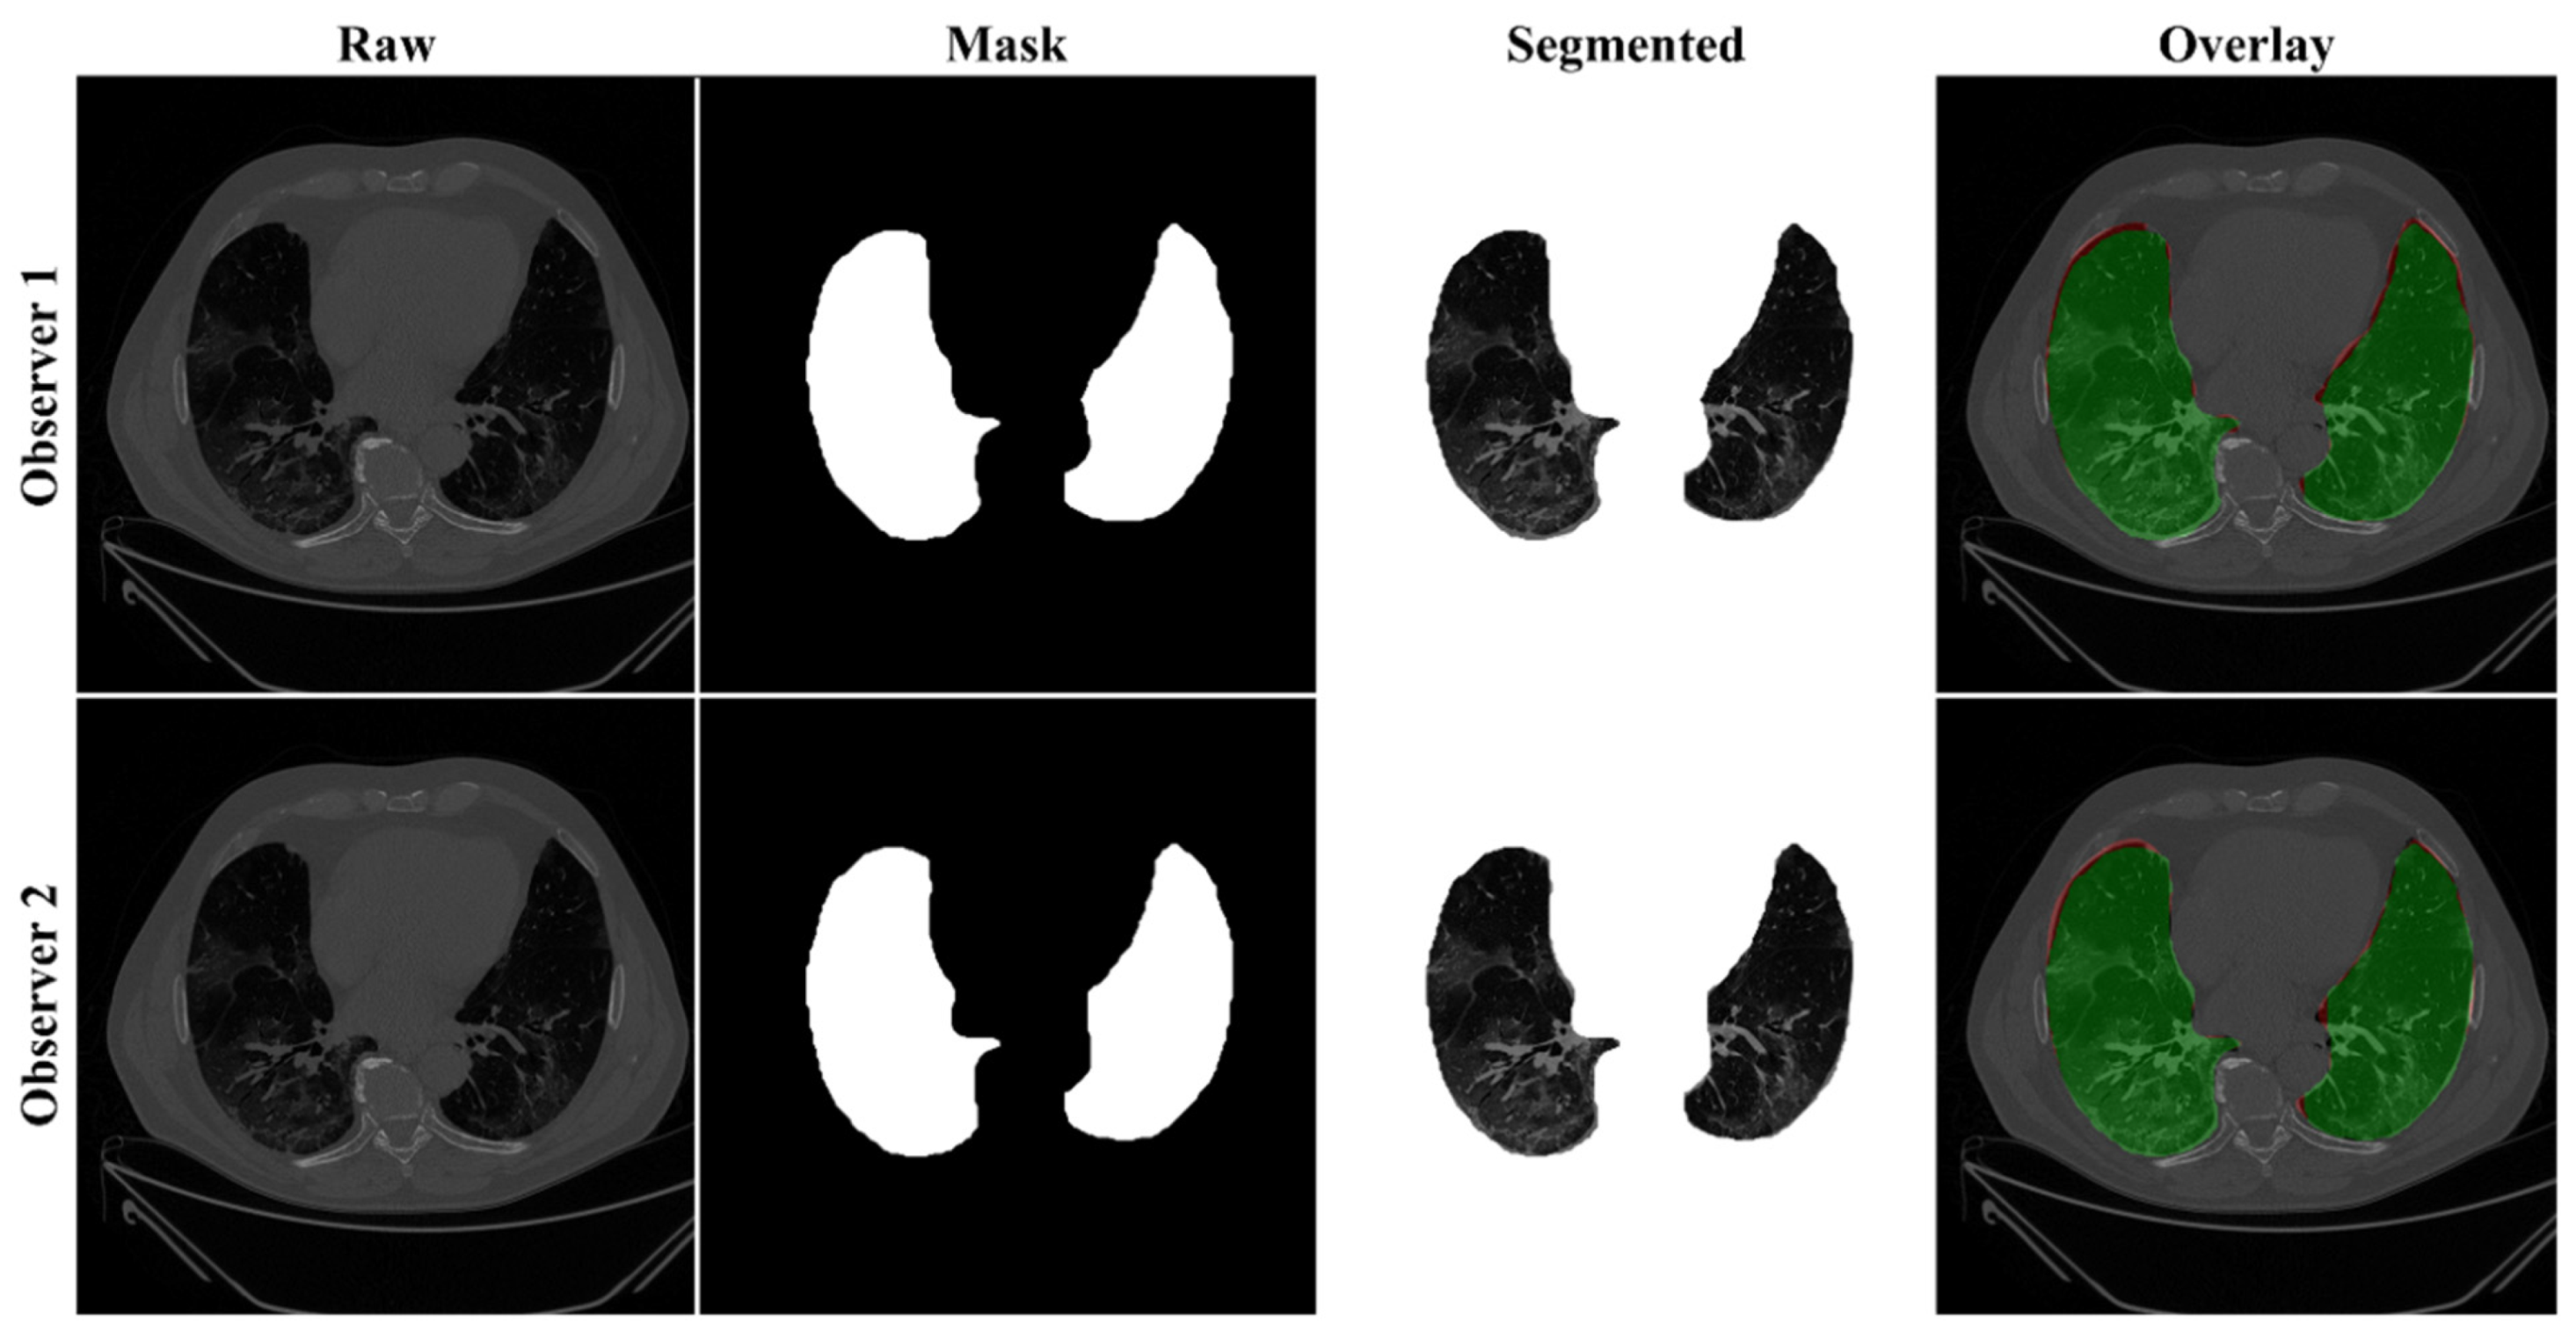

4.2.1. Lung Boundary and Long Axis Visualization